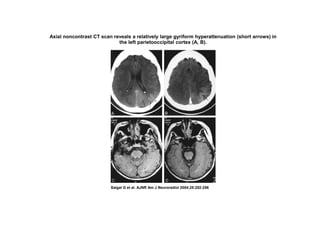

Axial noncontrast CT scan reveals a relatively large gyriform hyperattenuation (short arrows) in

the left parietooccipital cortex (A, B).

Saigal G et al. AJNR Am J Neuroradiol 2004;25:252-256